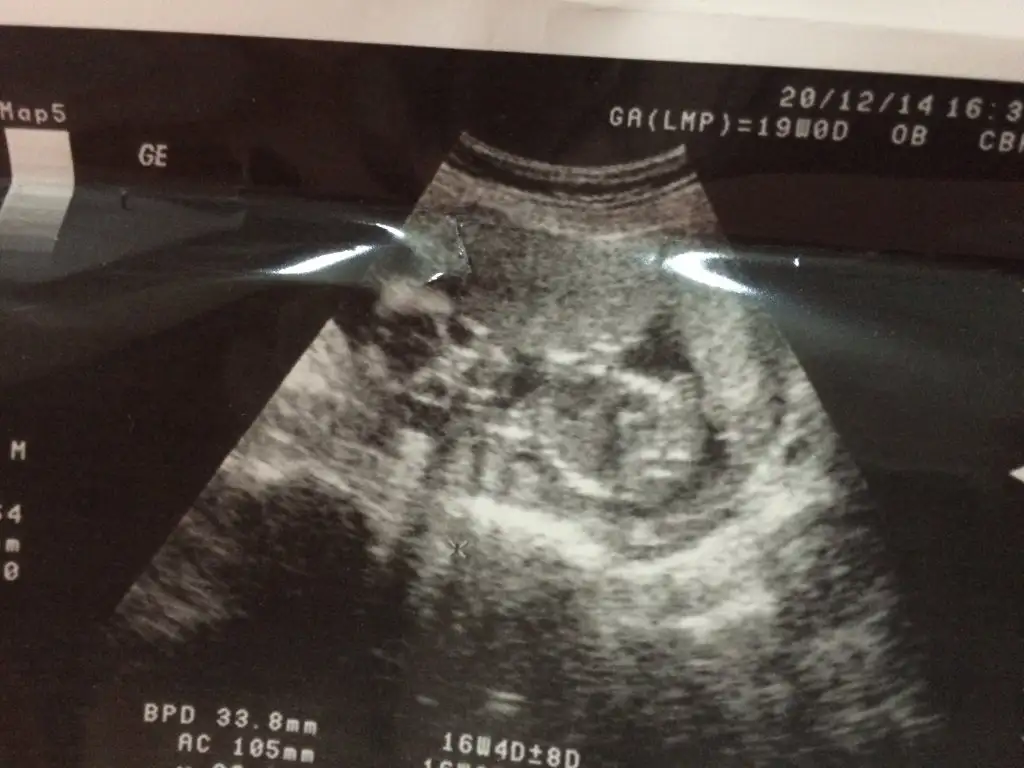

Canm sennki erkege benziyo sanki eminde degilim rahmin sadece hem sennki belli olmasi lazm 16 haftaKızlar benim bebeğim 16 haftalık sizce cinsiyeti ne ? Tahmin edebilenler lütfen yazsın şimdiden teşekkürler :)

Rahmim neye benziyor anlayamadım kontrole haftaya gidecem dr um söylemedi belli değil diye emin değil herhalde inşallah kızdır diye ümit ettim ama kısmet tüm belirtilerim hep kız Hep solda hissediyorum bebeğimi hayırlısı nasıl benzetiyorsunuz anlıyorsunuz cinsiyetini yorumun için teşekkürlerCanm sennki erkege benziyo sanki eminde degilim rahmin sadece hem sennki belli olmasi lazm 16 hafta

Bende onu bacağı gibi görüyorum hatta parmaklarıda var :)) 20 haftamdayım kesinleşmiştir zaten 20 haftaya kadar cinsiyet çok değişirmişya bende öyle duydumCanm yanls yazmsm tahmin sadece yazcaktimtam poposunn altinda bi cikinti var yukari dogru olunca erkek karsiya bakiyor ise kiz imis bnde oyle tahmin ettim rica ederim

Nasil 20 hafta cok uzun normalde 16. 17. Haftalarda soyleniyorBende kıza benzetmiştim aslında teşekkür ederim hayırlısıyla sağlıklı doğsunda doktoruma sordum ne zaman öğrenicez 20 . Haftada dediNasıl geçecek